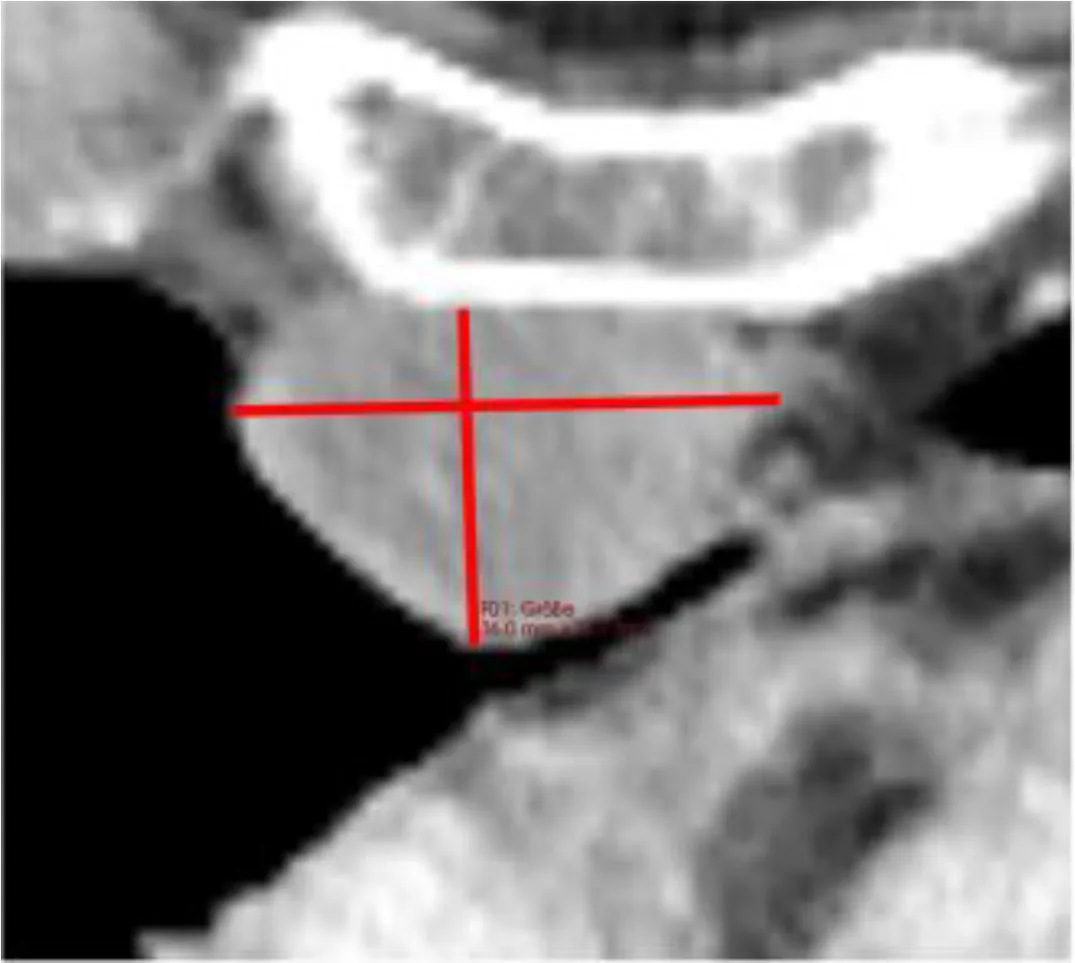

The reference value for correlation analysis was set to TBMTV. The correlation of total TBRECIL with total TBMTV was ρ=0.744 (0.546-0.863, p<0.001), and total TBLugano with total TBMTV ρ=0.741 (0.542-0.862, p<0.001). The correlation of TBRECIL or TBLugano with TBMTV was the lowest for extranodal disease. The results are illustrated in Figure 2. TBRECIL and TBLugano displayed a strong positive correlation for total (ρ=0.983 [0.967-0.992], p<0.001), nodal (ρ=0.938 [0.880-0.968], p<0.001) and extranodal TB (ρ=0.896 [0.803-0.947], p<0.001). Patient examples for the largest deviations are depicted in Figure 3.

Figure 3

Despite the numerically strong correlations among morphologic and metabolic methods, we identified several statistical outliers. We identified two patterns that led to the divergence in these patients: (1) disseminated lesions in extranodal disease, which led to underestimation by TBRECIL or TBLugano, and (2) metabolically inactive disease with large residual masses (e.g. after bridging therapy) that led to overestimation by TBRECIL or TBLugano when compared with TBMTV. These potential reasons of divergence among TB metrics should be considered as potential sources of bias when comparing results from different trials.